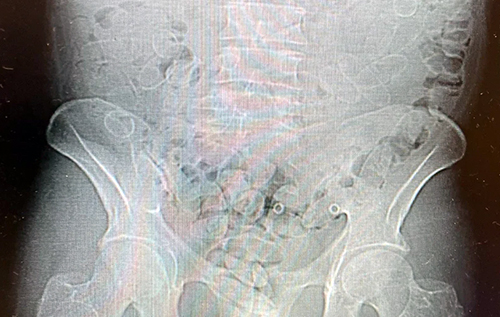

Митники помітили, що чоловік надзвичайно нервує, та запідозрили, що це далеко не увесь заборонений вантаж. Перевірка на УЗД підтвердила, що він ковтнув 88 капсул з кокаїном, сподіваючись провезти їх непоміченим. Сукупно у всіх 89 капсулах було приблизно 800 грамів наркотику.